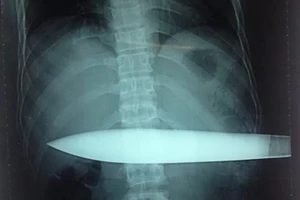

Nhập viện cấp cứu với con dao đâm lút 30 cm vào người